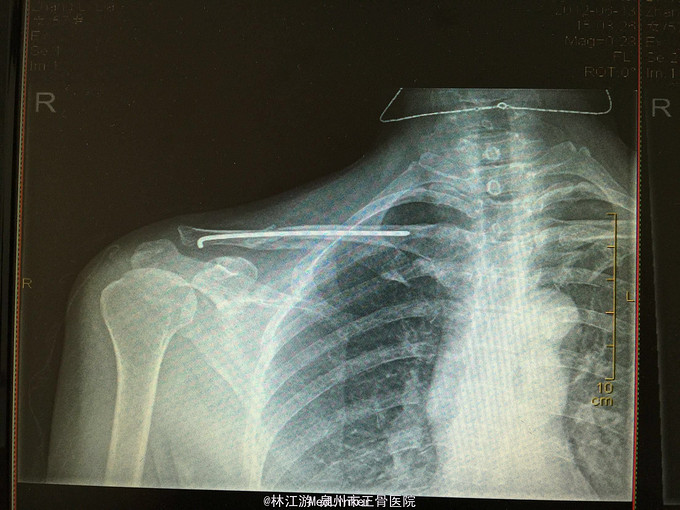

右锁骨粉碎性骨折闭合复位克氏针内固定术

右锁骨粉碎性骨折 行闭合复位克氏针内固定术

术后三年取内固定物,肢体活动正常